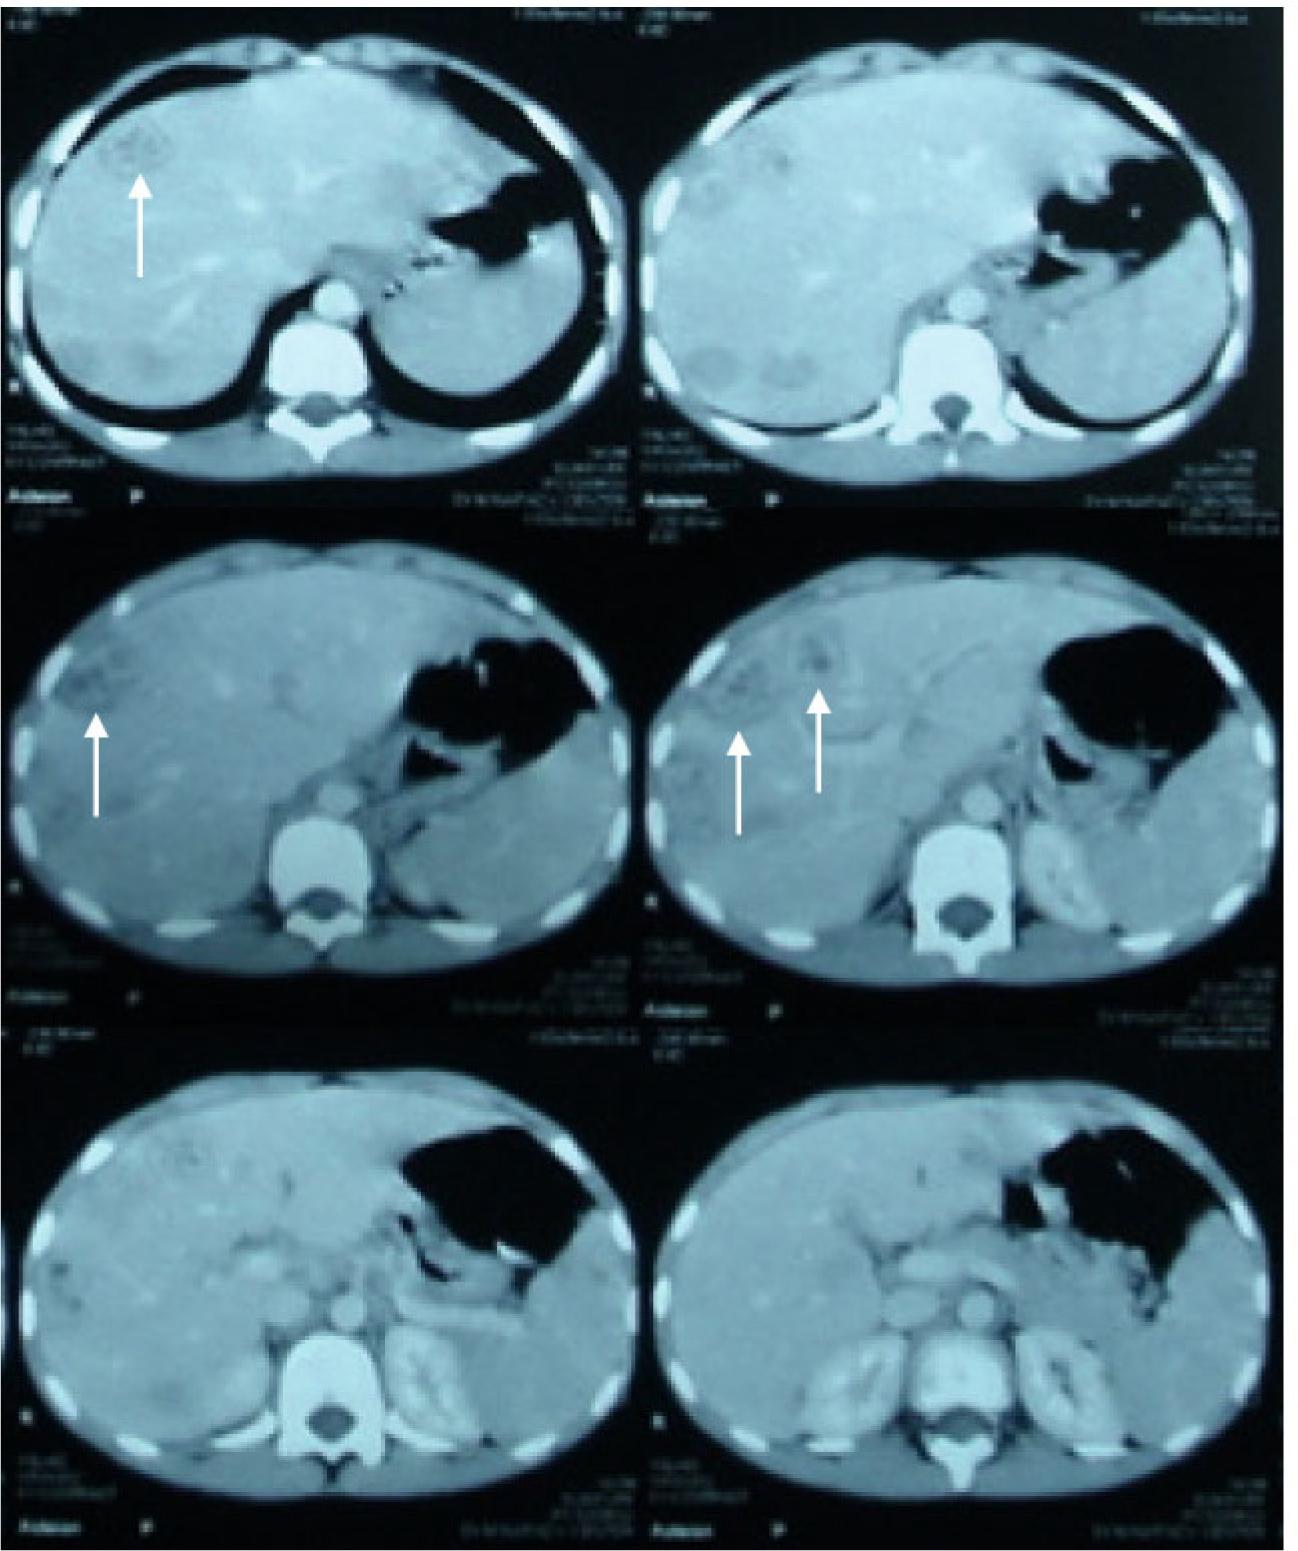

The upper abdominal CT revealed multiple discrete hypodense hepatic focal lesions appeared in both hepatic lobes, more pronounced at right lobe, some of them displaying peripheral ring wall enhancement (indicated by arrows) (Fig. 2). To evaluate the liver findings further, an ultrasound guided liver biopsy was performed. Histopathological analysis of the biopsy showed alteration of the normal architecture of the liver with fatty degeneration of liver cells (Fig. 3A). The biopsy demonstrates multiple inflammatory granulomas with eosinophilic infiltrations in liver tissues (Fig. 3B). The center of the granuloma showed multiple larvae (Fig. 3C and D). Despite symptomatic treatment in the form of antibiotics and antitussive, the patient continued to have severe dry cough. The patient file was referred to Parasitology Department, Assiut University seeking for medical advice. From the clinical manifestation, the detection of anti-Toxocara antibody and the presence of eosinophilic granulomatous lesions in both lung and liver attract the attention to the migrating larvae. These finding were highly suggestive of VLM syndrome. The patient was subsequently treated with albendazole (400 mg orally twice daily) for 2 weeks. There was a significant clinical improvement with resolution of cough, and eosinophilia was gradually subsided. The infiltrative shadows in both lung and liver disappeared completely.

Upper abdominal CT showing multiple discrete hypodense hepatic focal lesions in both hepatic lobes more obvious at right lobe

This case confirmed the findings of chest radiography and computed tomography demonstrated in the earlier publications (Inoue et al., 2002; Izumikawa et al., 2011). They have reported that granulomas or abscesses could appear as rounded nodules that are similar in appearance to other inflammatory lesions in chest radiography and lung CT. The sonographic findings of hepatic VLM syndrome were multiple ill-defined oval or elongated small nodular lesions scattered in the liver parenchyma (Holland et al., 2006; Ko et al., 2015). In this study, CT enabled better detectability and estimation of the distribution characteristics and the extent of the lesions than did chest radiography. Furthermore, CT represented unexpected features that chest radiography did not depict. Such features included reactive infiltration, parenchymal destruction, and granuloma or abscess formation.